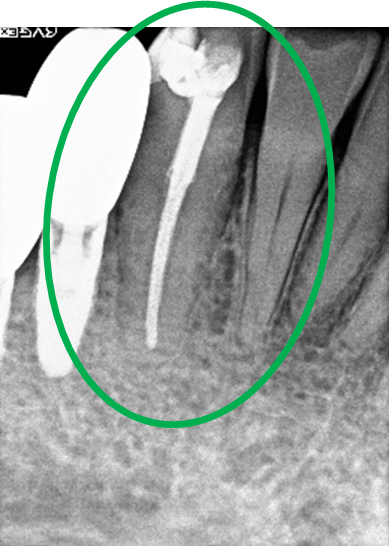

レントゲンを撮り詳しく診てみると、歯根が破折して保存することができず、抜歯する必要があることがわかりました。抜歯後、オールセラミックブリッジで補綴(欠損した部分を人工物で補う)しました。ブリッジの支台になっている後方の歯は、根尖性歯周炎(根の先端で問題を起こしている)でしたので、根管治療をしています。

所感

抜歯後、欠損部分を補う方法には、1本だけの部分入れ歯、ブリッジ、インプラントの3つの方法があります。この患者さんは、ブリッジを選択されました。メタルフリーの治療を希望されましたので、土台をファイバーコアにし、オールセラミックのブリッジをかぶせました。患者さんは、お口の中の金属を徐々に減らしていきたいということです。体全体の健康のことを考えると正しいことです。

オールセラミック冠(失活歯)1本:¥104,500(税込)

オールセラミック冠(生活歯)1本:¥93,500(税込)

ポンティック1本:¥93,500(税込)

合計:¥291,500(税込)

Before

After